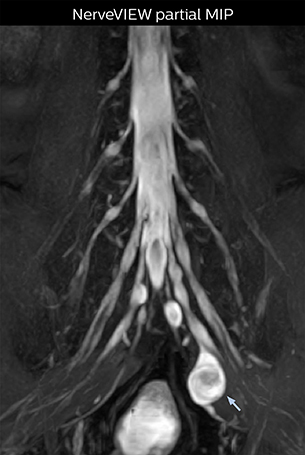

Northern Fukushima Medical Center (NFMC) Imaging Center uses the 3D NerveVIEW sequence for performing MR neurography, particularly in patients with pain and weakness in the lower limb. “It is included in about 20% of the approximately 150 lumbar spine MRI exams each month at NFMC, and can help us to determine if structures are impinging on the nerves,” says Hajime Tanji, RT, MRI technologist at NFMC.

“NerveVIEW is really useful for those cases where a nerve disorder is strongly suspected based on the clinical examination but our regular MRI images do not show any findings. These atypical herniations and spinal canal stenosis, occurring in 5% to 15% of the total lumbar herniation/stenosis cases are our main target when using NerveVIEW,” says Dr. Yabuki.

“The intra-luminal signal of veins, especially around the intervertebral space, can be suppressed well with NerveVIEW. As a result, we can easily observe the detailed nerve structure around the posterior ganglion,” he says. “This is why we use 3D NerveVIEW for intraforaminal stenosis and extraforaminal stenosis/herniation (lateral disc herniation). On the other hand, if herniation is suspected to exist inside the dorsal root ganglion (DRG), balanced TFE or ProSet-FFE is applied. NerveVIEW is not suitable for evaluating the median type of herniation.” The SE-EPI DWI-based method for MR neurography works well for large FOV exams like whole-body MRI, but focal examination of nerves is often limited by the attainable spatial resolution (both inplane and slice direction) and geometric distortion. “3D NerveVIEW achieves higher in-plane resolution – close to our other routine spine sequences – and the source images can be used instead of adding a fat-suppressed T2-weighted sequence,” Tanji says.

According to Tanji, methods such as ProSet FFE, STIR or 3D VISTA are anatomically nonselective because background signals, for instance from blood vessels, often interfere with nerves, which hampers evaluation of details, especially at the peripheral side of the nerves.

Implementing NerveVIEW without lengthening exam time “The source images of NerveVIEW exhibit a contrast similar to STIR or fat-suppressed T2-weighted images. So, in our neurography exams we are replacing the 2D T2-weighted coronal sequence with 3D NerveVIEW. With this, we add a lot of useful information without adding scan time. This is important for patients with severe lower extremity symptoms, as they often find it difficult to maintain still during the whole MRI examination, so the exam should be as short as possible.” “We have currently implemented 3D NerveVIEW on our Achieva 3.0T dStream MRI system only. Because the 3D NerveVIEW method is based on a background signal suppression technique, we decided to use the high SNR of our 3.0T MRI system for obtaining the best possible visualization of peripheral nerves,” says Tanji. “Where NerveVIEW of the lumbar plexus is currently used as a subroutine scan for patients with strong lower limb symptoms, its use for visualization of the brachial plexus, is currently limited to special cases such as schwannomas and neuritis, usually only 1 or 2 cases per month.”